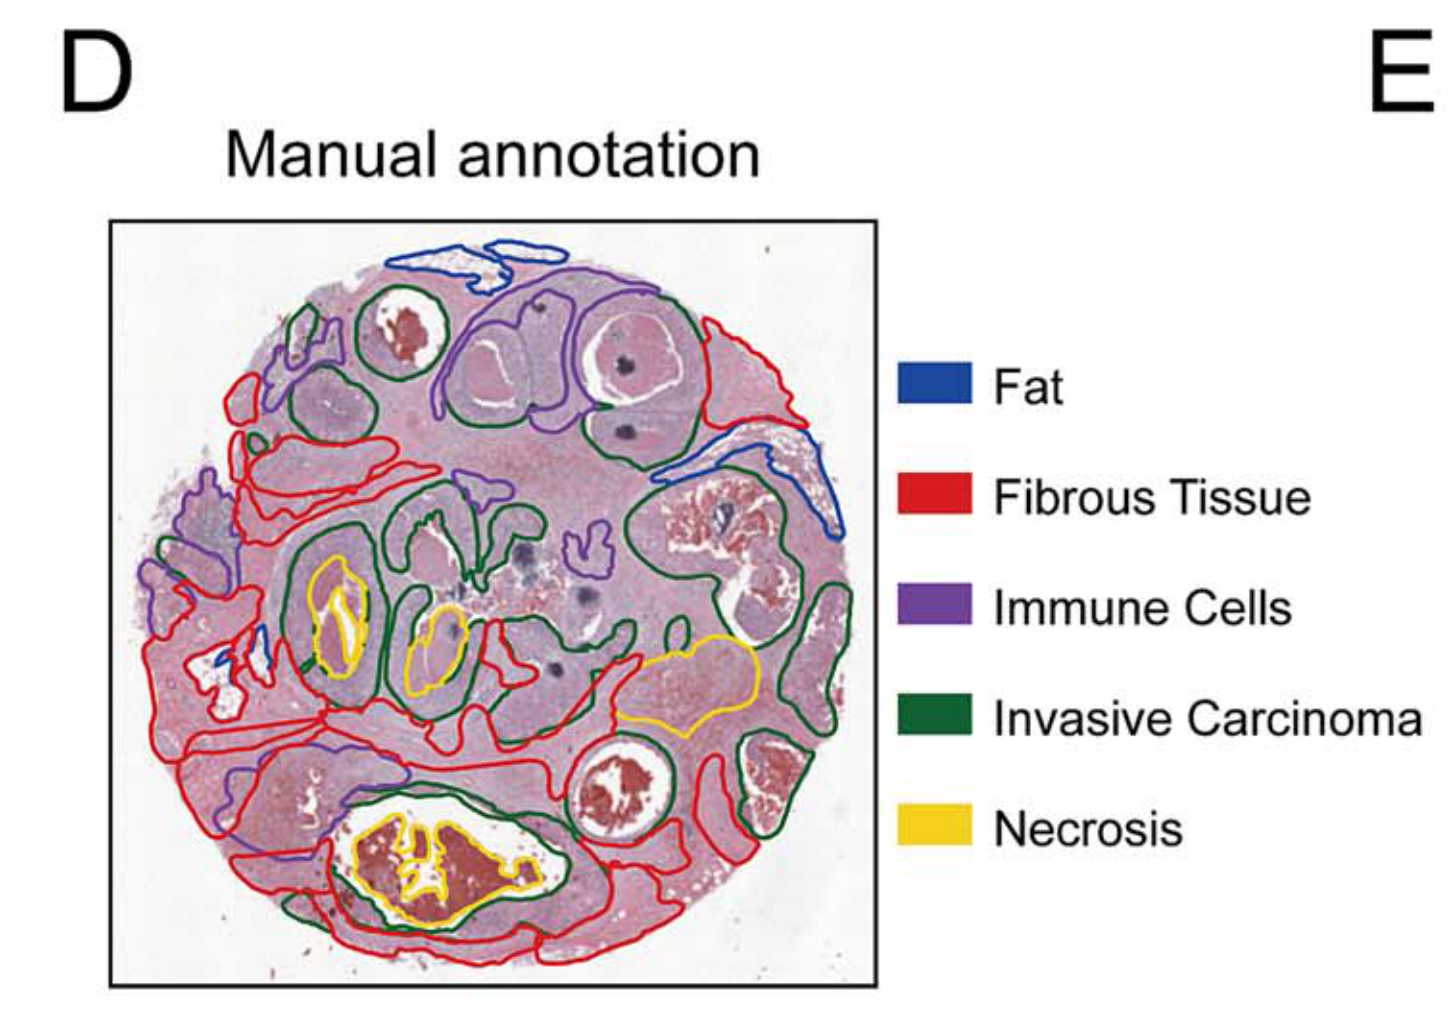

Jiang X. et al. - 2024

iIMPACT: integrating image and molecular profiles for spatial transcriptomics analysis

Condition Dimension

N/A

Data Components

Biological Annotation

Data

Metadata

None

Modality

Imaging-based

Resolution of observation

Multi-cellular

Visualized Elements

Observation

How are pathologist-defined tissue regions distributed across a cancer tissue section?

Biological

Tissue

Abstraction

Partial

Chart Type

Histological image

Communicative/Contextualization

Highlighting

Comparative Design

None

Layout

Spatial : Physical

Scalability Strategy

None (Item-level)

Wei R. et al. - 2022

Spatial charting of single-cell transcriptomes in tissues

Condition Dimension

N/A

Data Components

Biological Annotation

Data

Metadata

None

Modality

Sequencing-based

Resolution of observation

Functional tissue unit

Visualized Elements

Observation

Biological

Tissue

Abstraction

None

Chart Type

Histological image

Communicative/Contextualization

Annotation

Comparative Design

None

Layout

Spatial : Physical

Scalability Strategy

None (Item-level)

Where are tumor regions located within the spatial architecture of a tissue section?